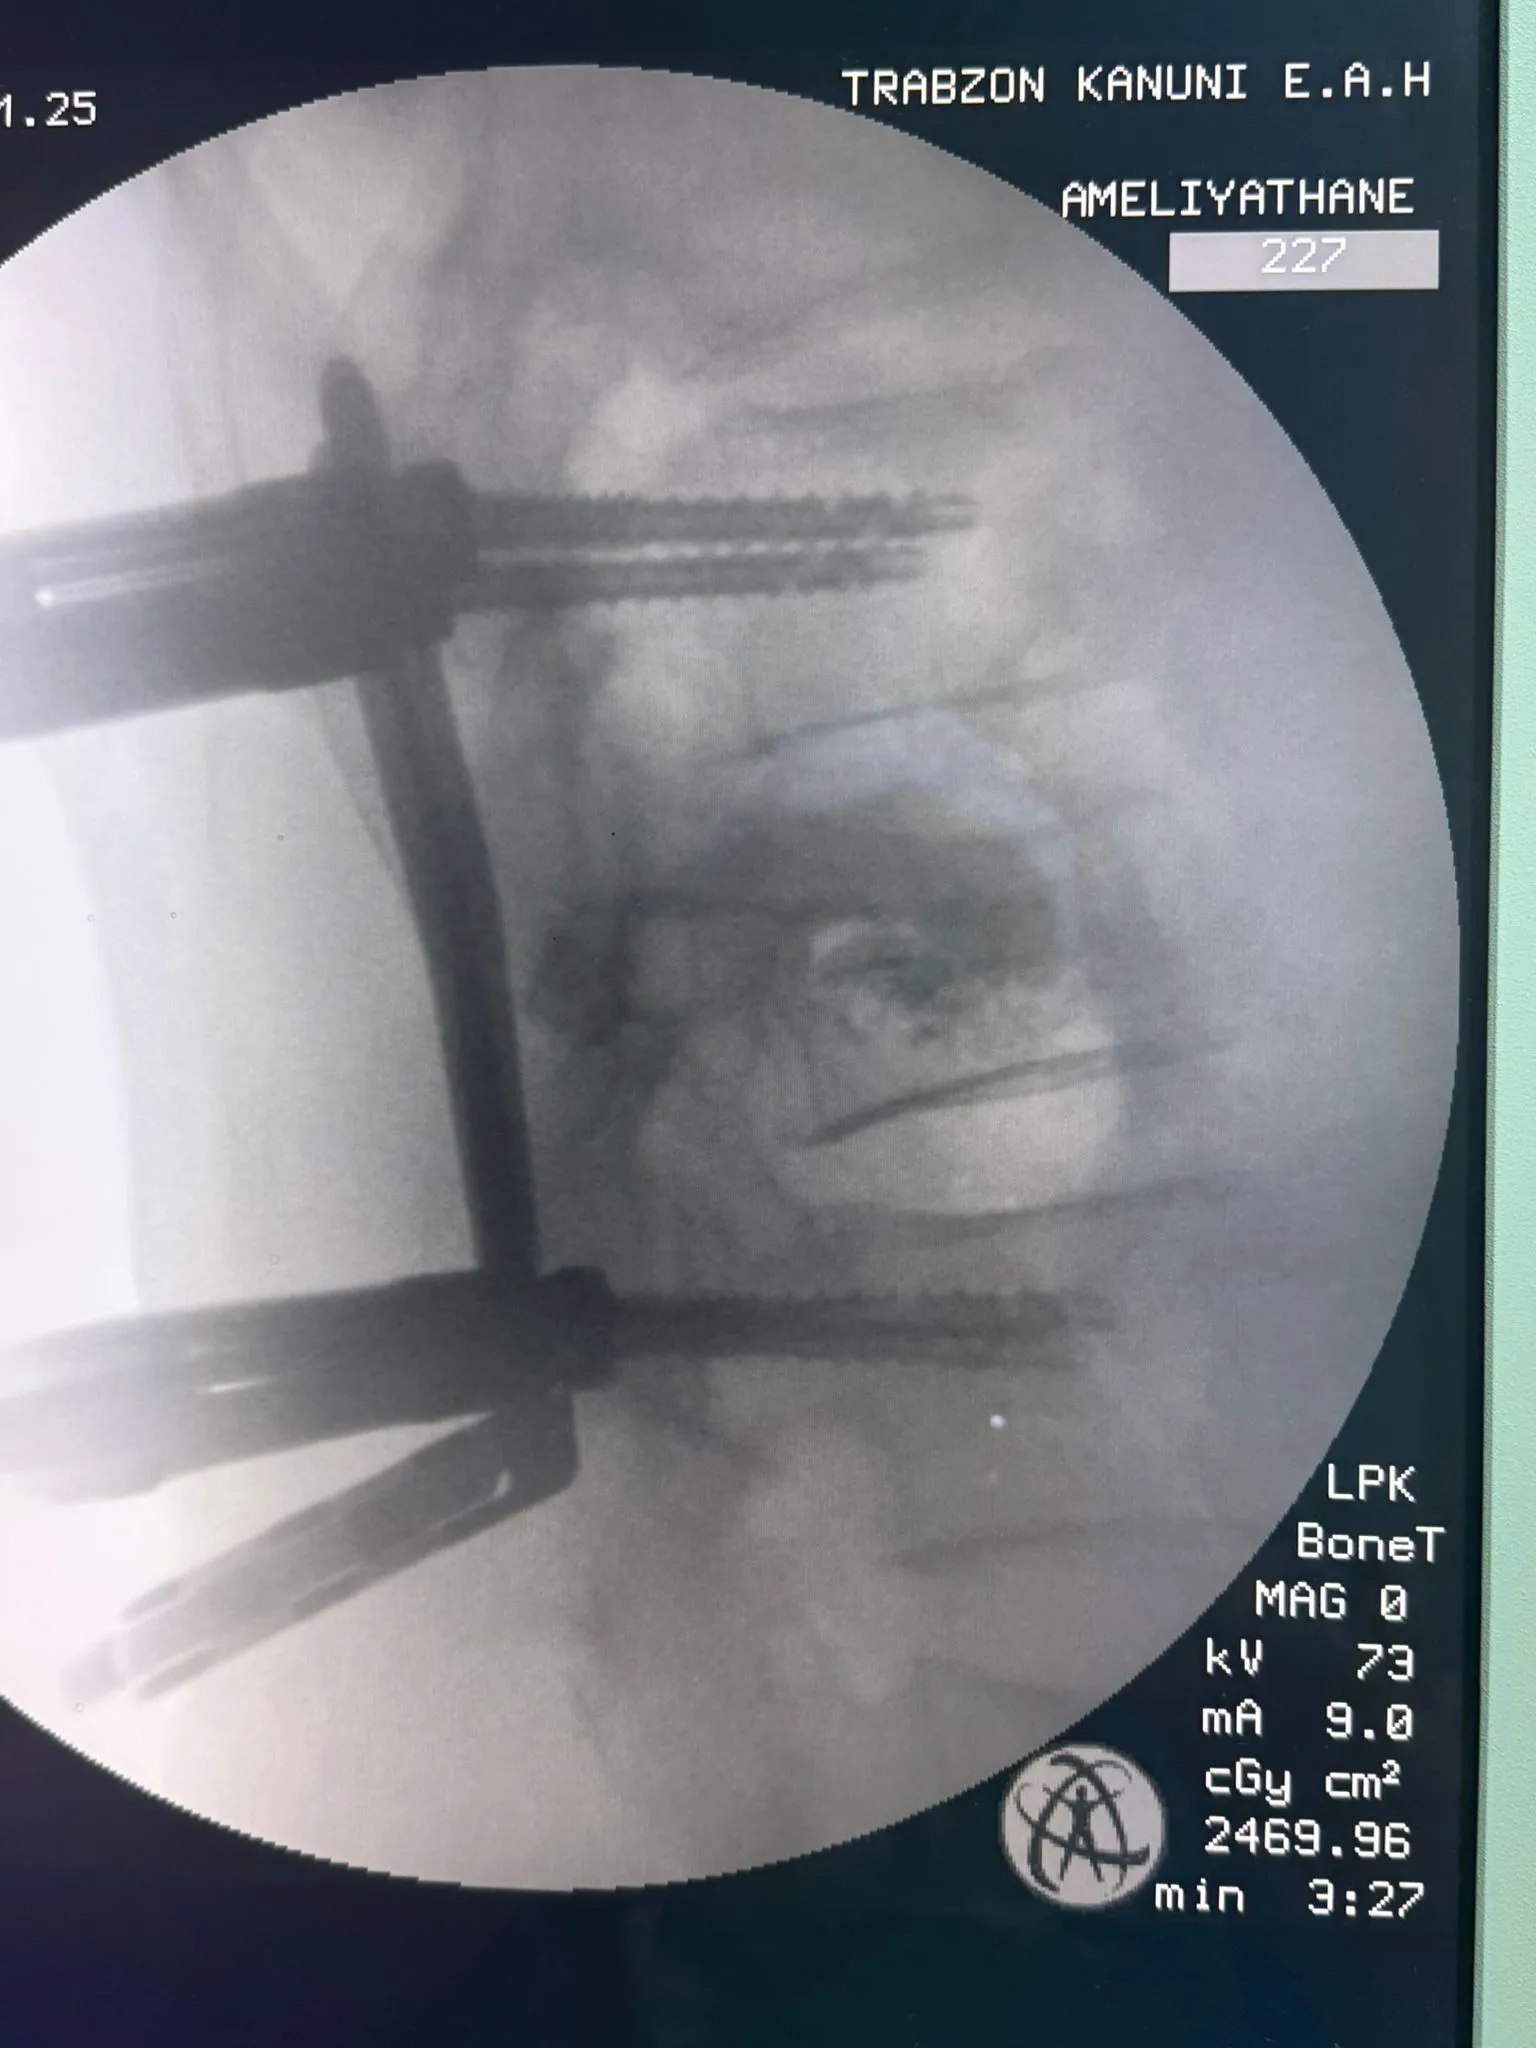

Gelişmiş tekniklerle gerçekleştirilen omurga vidalama ameliyatı, hem hasta hem de tıp camiası açısından örnek bir uygulama oldu.

Operasyonu gerçekleştiren Beyin ve Sinir Cerrahisi Uzmanı Dr. Gürkan Uzun, ameliyatın detayları hakkında bilgi verdi. Dr. Uzun, kullanılan cerrahi yöntemin avantajlarını şöyle sıraladı:

Küçük kesi bölgesi sayesinde daha az ağrı

Düşük enfeksiyon riski

Hızlı iyileşme süreci

Günlük yaşama erken dönüş

Dr. Uzun ayrıca, “Bu teknikle hastalarımıza daha konforlu bir iyileşme süreci sunabiliyoruz. Başarılı sonuçlar almaya devam ediyoruz” dedi.